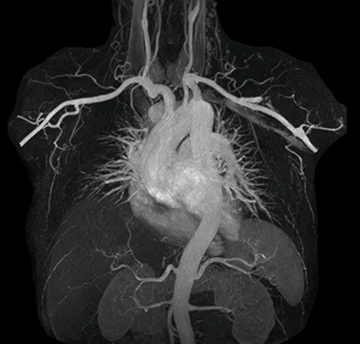

“In MRA, the capacity to acquire a sequence in a single breathhold provides images that are motion-free and high in contrast and detail, advantages that aid in diagnosis,” he says. “With Compressed SENSE, we can reduce the time for the single breath-hold to just 2-3 seconds. Before Ingenia Ambition and Compressed SENSE, the breath-hold requirement was about 8 to 9 seconds, which was too long for some patients.”

“In our peripheral MRA run-off studies with Ambition we realize key benefits, including outstanding image quality and significantly reduced breath-hold and scan times, which not only benefit the patient, but also provide the opportunity to add sequences that could aid in diagnosis,” Dr. Peña says.

“Before we had Ingenia Ambition, our CE-MRA run-off studies would first acquire a dynamic pre-contrast scan with 20-25-second breath-holds, then inject the contrast, do another acquisition and then subtract the two,” says Avila. “Now, mDIXON XD allows us to complete the study in just one single pass – without need for a pre-exam – which eliminates subtraction artifacts and almost halves the scan time. In addition, mDIXON provides much better background suppression, which really improves vesselto-background contrast. And, thanks to Compressed SENSE, the single breath-hold is not long and we improve image resolution.”

The subtractionless peripheral MR angiography shows improved vessel-to-background contrast and high resolution. Ingenia Ambition 1.5T.

The images obtained with Ingenia Ambition show large coverage and high uniform signal. More vessels are visible than in a previous exam of the same patient on Achieva. The movies show a higher temporal resolution in the Ambition acquisition than in a previous Achieva 1.5T exam. Both exams use a FOV of 300 mm and voxel height and width of 0.78 mm.

The team at Miami Cardiac & Vascular Institute also appreciates Ingenia Ambition’s capabilities for fast dynamic CE-MRA. “With 4D TRAK XD, we get much better temporal and spatial resolution. Previously, with the Achieva we needed 6 seconds per dynamic, but now we can shorten that to 2 seconds per dynamic,” Avila says. “As a result, we can see the transition from arterial to venous phase with much higher temporal resolution. This is important, for example, for imaging arteriovenous malformations, which are quite vascular.”

“On our previous system we really had to sacrifice image resolution to get to 5- or 6-second temporal resolution, while now – using 4D TRAK XD on Ambition – we no longer have to sacrifice image quality,” Dr. Peña says.